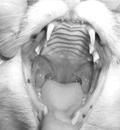

10-1. 치은염-구내염-인두염 복합증 (GSPC, Gingivitis-stomatitis-pharyngitis complex)

- 고양이 치은염-구내염-인두염 복합증 질환은 고양이의 구강 내 연부 조직의 증식, 궤양, 염증을 유발하는 흔한 질환입니다. 주로 순종 고양이에서 다발합니다. 구강 내 다발하는 부위는 혀 입천장 점막과 볼점막등이 있습니다.

병변은 구강점막, 점막하 조직의 림프구와 형질세포의 침윤이 특징입니다.

원인은 알려져 있지 않지만, 세균 플라그 또는 치아 일부에 대한 과민반응 같은 면역 매개성 요인을 포함한 여러 가지 요소가 작용합니다. 발치가 권장되며 주기적인 스케일링과 폴리싱도 권장됩니다.